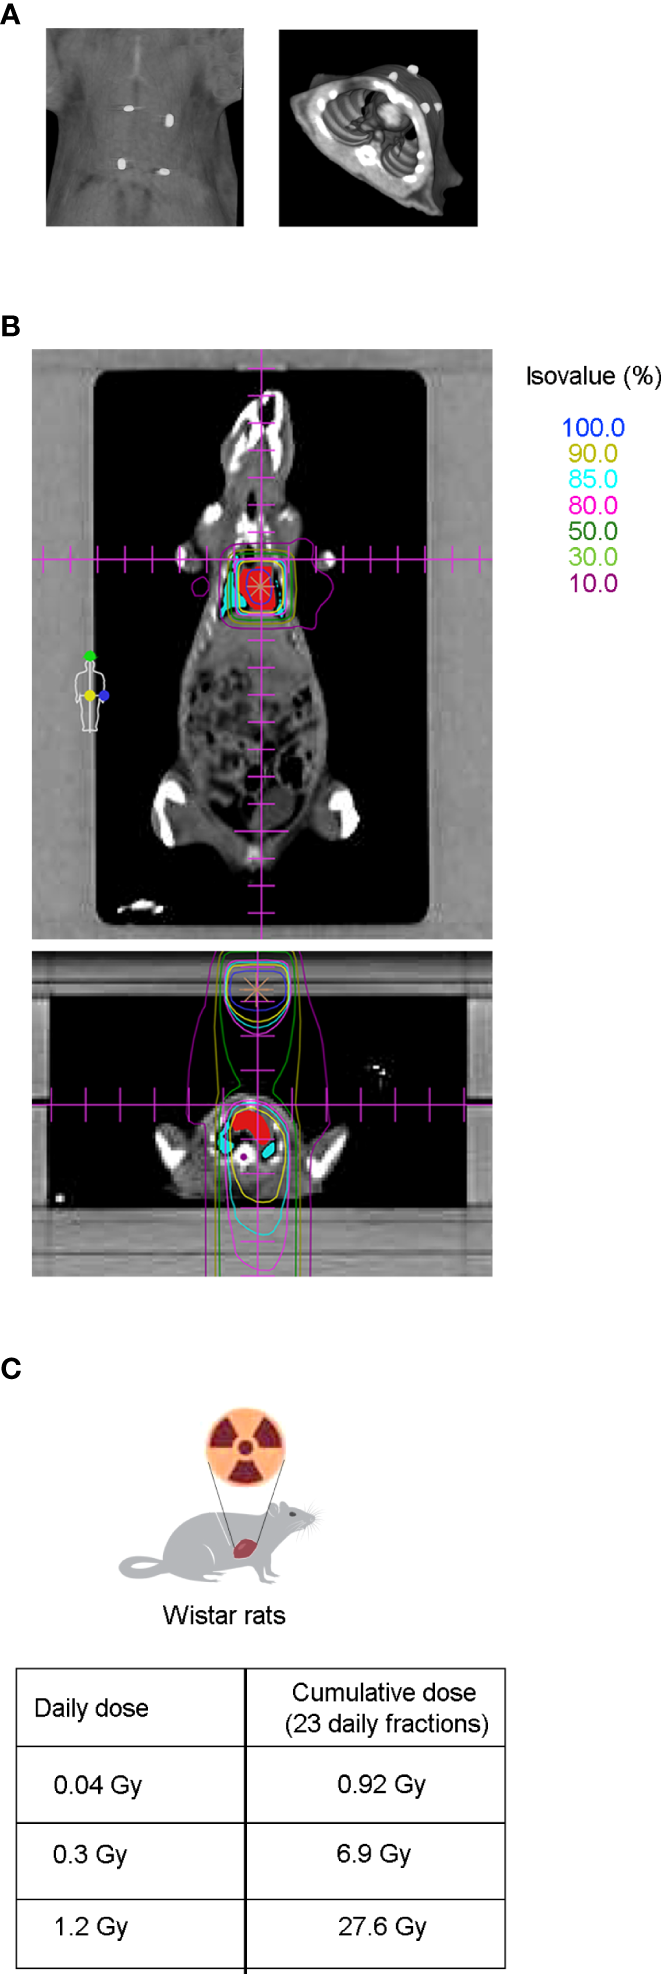

To evaluate the effect of radiotherapy on cardiac dysfunction, the hearts of adult Wistar rats were exposed to photon beams using a medical electron linear accelerator. Reference points were indicated with fiducial markers placed over the skin, followed by a CT simulation (Figure 1A) and radiotherapy planning (Figure 1B). The rat hearts were cumulatively exposed to 0.92, 6.9, or 27.6 Gy, covering a range from moderate to high doses of IR that are clinically relevant in a cardiac context for oncological patients who undergo radiotherapy. Importantly, these cumulative doses were administered in a fractionated scheme, meaning that the rat hearts were exposed daily to doses of 0.04, 0.3, or 1.2 Gy for 23 consecutive days (excluding weekends), to mimic the conventional radiotherapy plan (Figure 1C). A longitudinal study of cardiac structure and function by echocardiography was conducted (Figures 2 , S1–S4). At 12 months after the end of radiotherapy, the chamber dimensions, LV systolic function, right ventricular function, and LV diastolic parameters were measured and no significant differences were observed (Supplementary Figures S1–S4), except for the relative percentage of GLS. According to our data, GLS presented a significant decrease of 18.5, 29.6, and 28.1% for the daily doses of 0.04, 0.3, and 1.2 Gy administered for 23 days, respectively, when compared to the sham-irradiated experimental group (Figure 2). At 9 months, no changes in GLS were observed for any cumulative dose (Figure 2).

Figure 1

CT simulation and dose distribution planning preceded thoracic radiation therapy in Wistar rats. (A) After echocardiography, radiopaque fiducial markers were placed over the shaved skin of the animal (left panel) to correlate the CT images to the external anatomical references used during animal setup prior to RT (right panel). (B) Coronal (upper panel) and axial view (lower panel) from CT-based radiation therapy planning dose distribution. Isodose curves are shown in a range of 100% (dark blue), to 10% (dark pink), being the most internal ones: 90% (yellow), 85% (light blue) and 80% (light pink), for the prescribed doses of 0.04, 0.3, and 1.2 Gy. Target heart structures (red) and organs at risk such as the lungs (blue) and medulla (purple) are also shown. (C) Twelve to fourteen week old Wistar rats were cumulatively irradiated with 0.92, 6.9, or 27.6 Gy, administered in a fractionated scheme of 23 daily doses of 0.04, 0.3, or 1.2 Gy, respectively.